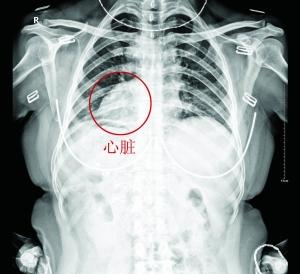

刘女士的心脏长在右侧

贵阳市一名50多岁女子因患胆结石去医院拍照检查,医生发现她心脏长在右侧胸部,进而确认她是一名“镜面人”。据悉,“镜面人”出现的几率为百万分之一。

昨日上午,因胆结石病发疼痛,家住贵阳市南明区的刘女士到贵阳结石病医院诊治。拍CT照后,医生发现她的心脏长在右胸。进一步检查后,发现该女士与常人相比,体内多个器官都完全长反,进而才确认她是罕见的“镜面人”。

据医生介绍,“镜面人”又称“镜子人”或“镜像人”,即心脏、肝脏、脾脏、胆等器官的位置与正常人相反,心脏、脾脏在右边,肝脏位于左边,心、肝、脾的位置好像是正常脏器的镜中像。目前,医学上对“镜面人”现象的成因还没科学定论。有医学专家认为,“镜面人”是在人体胚胎发育过程中,与父母体内基因的一个位点同时出现突变有关,其发生几率大约为百万分之一。另外,“镜面人”虽然内脏全部错位,但只是位置发生变化,相互间的关系并未改变,因此生理功能与正常人一样,对健康与生活都没有太大影响。